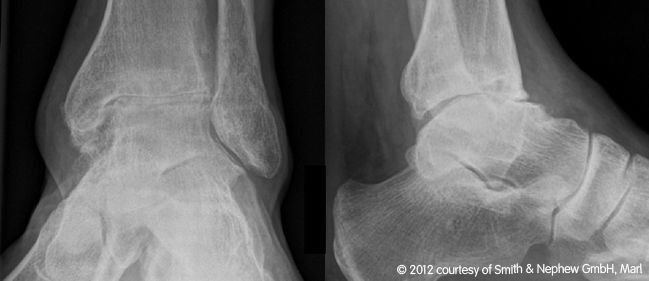

Obere Sprunggelenksendoprothese

Seit 2003 werden in unserer orthopädischen Abteilung in geeigneten Fällen die arthrotisch oder unfallbedingt zerstörten Sprunggelenke durch ein „künstliches Sprunggelenk“ ersetzt.

Wir verwenden dabei die von Prof. Hintermann entwickelte HINTEGRA-Totalendoprothese ,die zementfrei mit nur geringer Knochenresektion eingebaut wird.

Der Vorteil gegenüber der Arthrodese (Versteifung) ist evident: die Beweglichkeit im oberen Sprunggelenk bleibt erhalten oder wird teilweise wiedergewonnen, die bei der Versteifung gefürchtete Arthrose der benachbarten Gelenke wird vermieden. Die überwiegende Zahl der von uns behandelten Patienten ist bisher hoch zufrieden.